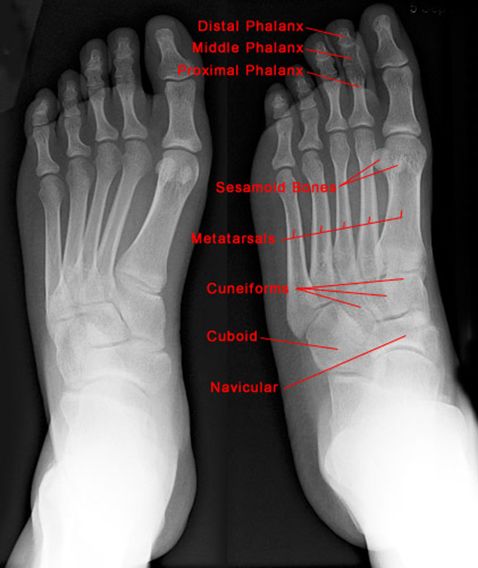

正常足侧位片

正常足正位片

跟骨骨折

Jones Fracture

第五跖骨基底部骨折

易漏诊

不制动易致骨不连

跖骨骨折